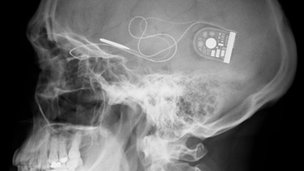

Κατά την “επαναστατική” αυτή επέμβαση, ένα υπέρλεπτο chip 3 χιλιοστών, το οποίο περιέχει 1.500 φωτοευαίσθητα pixels, τοποθετείται πίσω από τον αμφιβληστροειδή, ενώ συνδέεται μέσω ενός καλωδίου με μία μονάδα ελέγχου που τοποθετείται κάτω από το δέρμα πίσω από το αυτί.

Όταν το φως εισέρχεται στο μάτι και φτάνει στο chip, “ενεργοποιεί” τα pixels, τα οποία στέλνουν ηλεκτρονικά σήματα στο οπτικό νεύρo και μετέπειτα στον εγκέφαλο. Η “ευαισθησία” του τσιπ μπορεί να μεταβληθεί με τη βοήθεια μίας εξωτερικής μονάδας ισχύος που συνδέεται με αυτό μέσω ενός μαγνητικού δίσκου στο τριχωτό της κεφαλής.